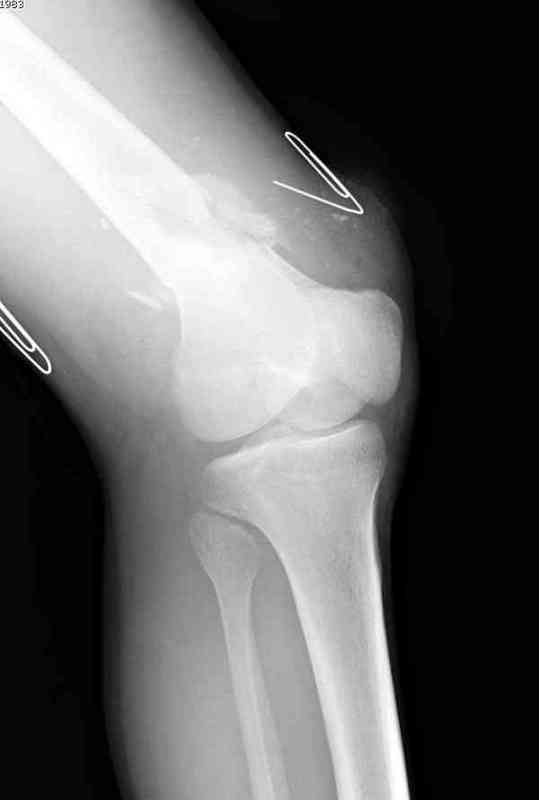

Пострадавшему 23, пистолетная огнестрельная не кроветочащая рана, меньше одного см диаметром, входное отверстие расположено латерально, и выход передне-медиально, и еще имеется второе пулевое ранение правой navicular bone с этой стороны.

Несмотря на сниженный до 0.9 BI-ankle-brachial-index (обязательное, недорогое исследование при подозрении на повреждение сосудов, рассчитанный по разнице давления в нижней и верхней конечности), последующее КТ ангиограмма не подтвердила повреждения артериальных сосудов.

При близости сосудов к многооскольчатому повреждению костей, сперва необходимо удостовериться в наличии повреждения сосудов без применения турникета.

Сосудистые повреждения часто приводят к увеличению

давления в компартментах, мониторинг на голени показал увеличение, и поэтому сделана профилактическая латеральная фасциотомия.